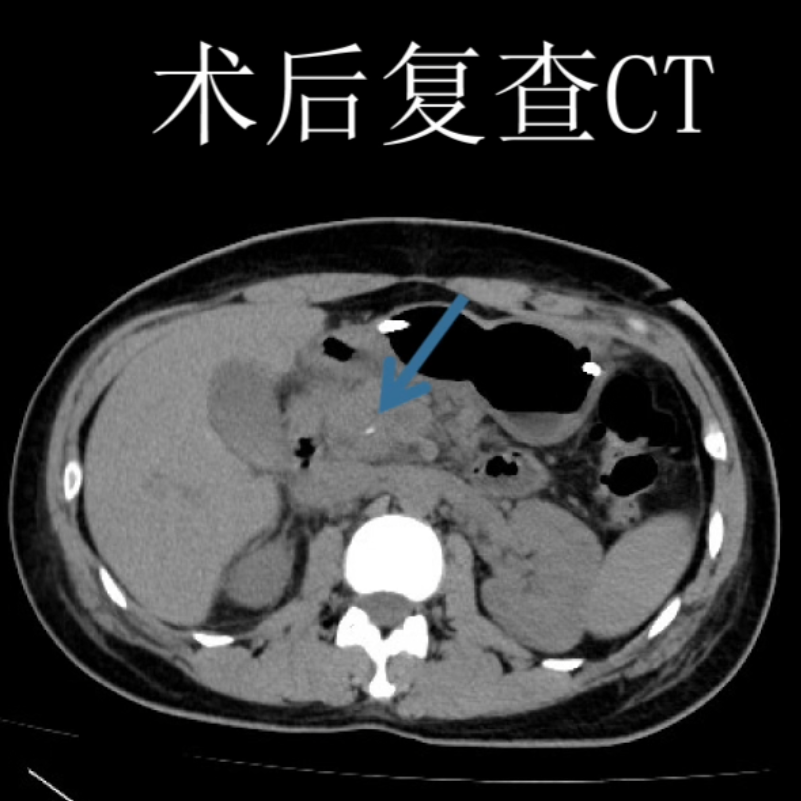

田毅峰教授、陈实教授经过数字成像智能评估后,准确分析并制定出微创下切除肿瘤的最便捷路径,为赵某实施机器人辅助胰体尾脾切除术,术中借助机器人高清的三维视野、灵活的机械臂、精细操作,在狭小的空间中最终完整切除肿瘤,成功实现微创手术,术后恢复良好,患者腹部只留下4cm的隐匿伤口,做到“大切除、小伤口”,充分体现了机器人智能系统在胰腺外科中的极致优势。

术前术后对比图